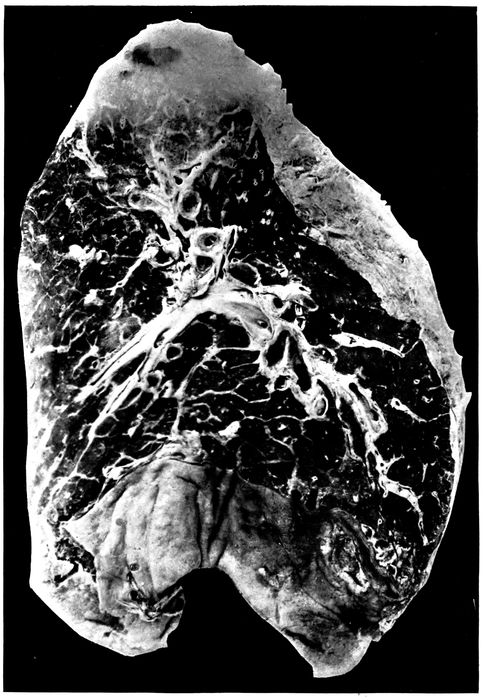

| 25. | Advanced bronchiectasis throughout lower left lobe | 258 |